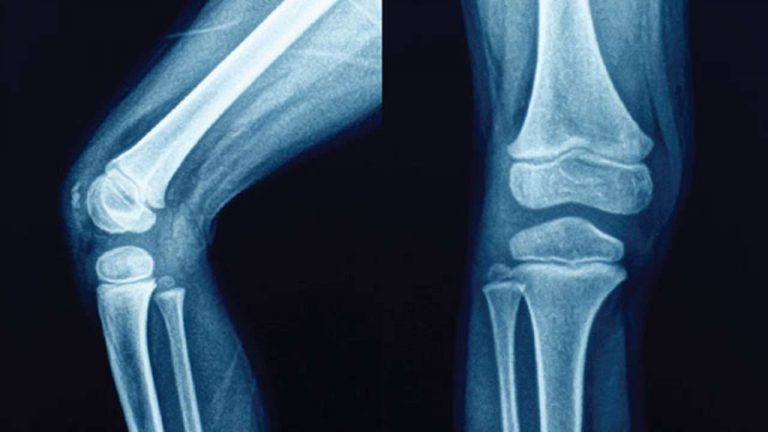

التوقف المشترك: المفصل المفصلي يشبه الباب، يفتح ويغلق في اتجاه واحد على طول طائرة واحدة. من الأمثلة على ذلك مفصل الكوع ومفصل الركبة.